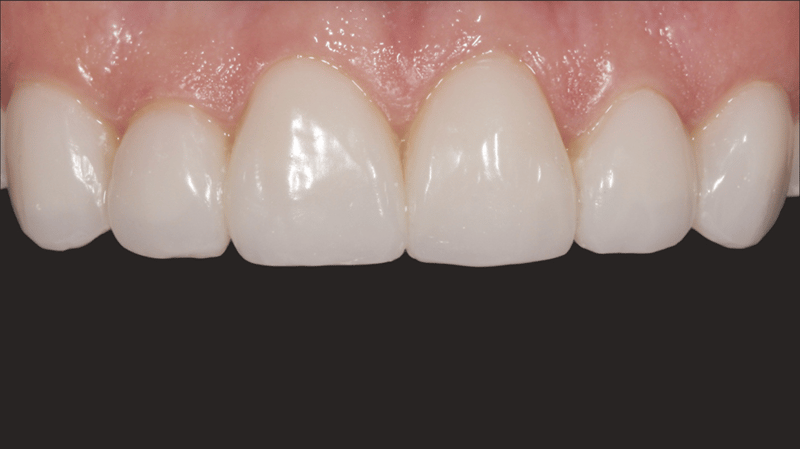

- Finale Restauration: Endgültige Zementierung mit einer stabilen und ästhetisch ansprechenden Veneer-Versorgung.

Mit dem durchgeführten Behandlungsprotokoll konnten die ästhetischen Anforderungen der Patientin erfüllt werden. Die Verfärbung der oberen Frontzähne wurde kaschiert und ein natürliches, auf die unteren Frontzähne abgestimmtes, Erscheinungsbild wurde erzielt. Die Verwendung von direkten Non-Prep-Kompositveneers war dabei eine konservative, höchst effektive Lösung, die sowohl den finanziellen Möglichkeiten der Patientin als auch ihrem Wunsch nach minimal-invasiven Methoden Rechnung trug.